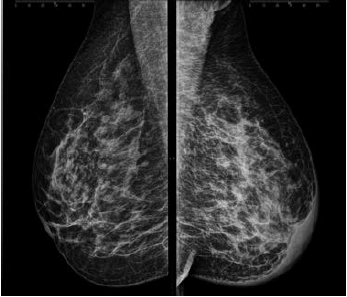

Uma paciente de 46 anos realizou esta mamografia.

Assinale a alternativa que contém a descrição e a classificação BIRADS correspondente.

A

Mamas densas sem evidência de nódulos visíveis ou linfonodomegalia axilar. BIRADS 1.

B

Assimetria focal e linfonodos intramamários no QSE da mama direita. BIRADS 3.

C

Infiltração cutânea e aumento difuso da densidade da mama esquerda. BIRADS 5.

D

Ectasia ductal retroareolar e linfonodo intramário no QSE da mama esquerda. BIRADS 2.

E

Assimetria focal no QSE e espessamento cutâneo retroareolar da mama direita. BIRADS 5.